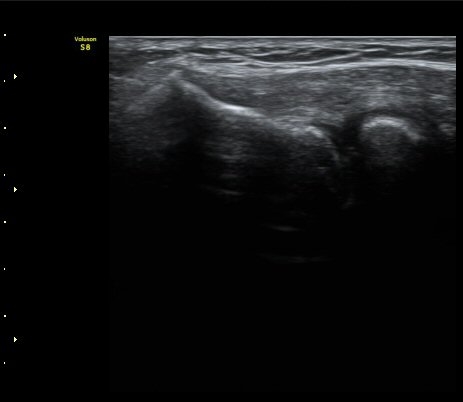

ÃÊÀ½ÆÄ °Ë»ç